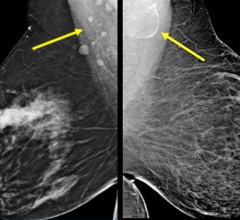

August 6, 2009 - The use of digital breast tomosynthesis and full-field digital mammography (FFDM) combined may be associated with a substantial decrease in recall rate, according to a study performed at UPMC in Pittsburgh, Penn., published in the American Roentgen Ray Society.

An estimated 10 percent of women in the United States are recalled for a second mammogram after an abnormality is detected on the first one. Some researchers believe that digital breast tomosynthesis depicts the breast tissue in a way which may allow radiologists to identify some tumors which could be missed with standard two-dimensional mammography.

In the study, 125 patients were evaluated using a combined method of digital breast tomosynthesis and standard digital mammography. The use of digital breast tomosynthesis and FFDM was associated with a 30 percent reduction in recall rate for cancer-free examinations that would have led to recall if FFDM had been used alone, reported Jules H. Sumkin, M.D., one of the authors of the study.